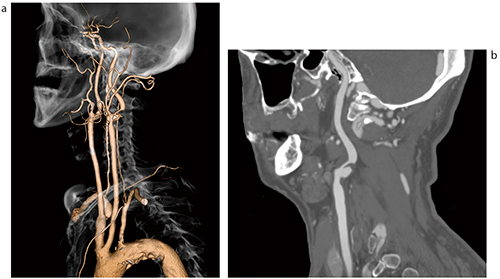

頸部には重要な血管が複数走行しているが,その中でも総頸動脈,内頸・外頸動脈,椎骨動脈が頭部の栄養血管として重要なのは言うまでもない。造影CTにおいて,これらの血管を効率的に描出し,診断や治療前に情報提供できることが,画像解析装置に求められる。当社が開発する汎用セグメンテーションツールである“リージョングローイング”は,どの血管に対しても有効であるが,頸部において,高いCT値物質が複雑に絡み合う骨と造影血管をマウスクリックで簡単かつ高速に分離することが可能である(図1)。このような技術を特殊なものとして扱わず,標準機能として搭載しており,想定されないような血管走行,または骨格の構造に対して融通が利くようにしている。

図1 総頸動脈セグメンテーションとCPR表示

狭窄部位では,CPR機能により血管の直交方向のCT画像(オブリーク)を再構築し,狭窄部の血管壁を観察する。グレイスケールでは判定できないような微妙なコントラストの場合は,クリアウインドウ機能で微細なコントラスト変化をカラーリングによってとらえ,CT値によるプラークの評価を容易にする(クリアウインドウ機能は特許取得ずみ)(図2)。

このように,セグメンテーションやCPR機能による構造解析,さらにカラーリングによるプラークの性状分析など,CT画像から得られる情報を最大限に,かつ短時間で得ることが可能である。